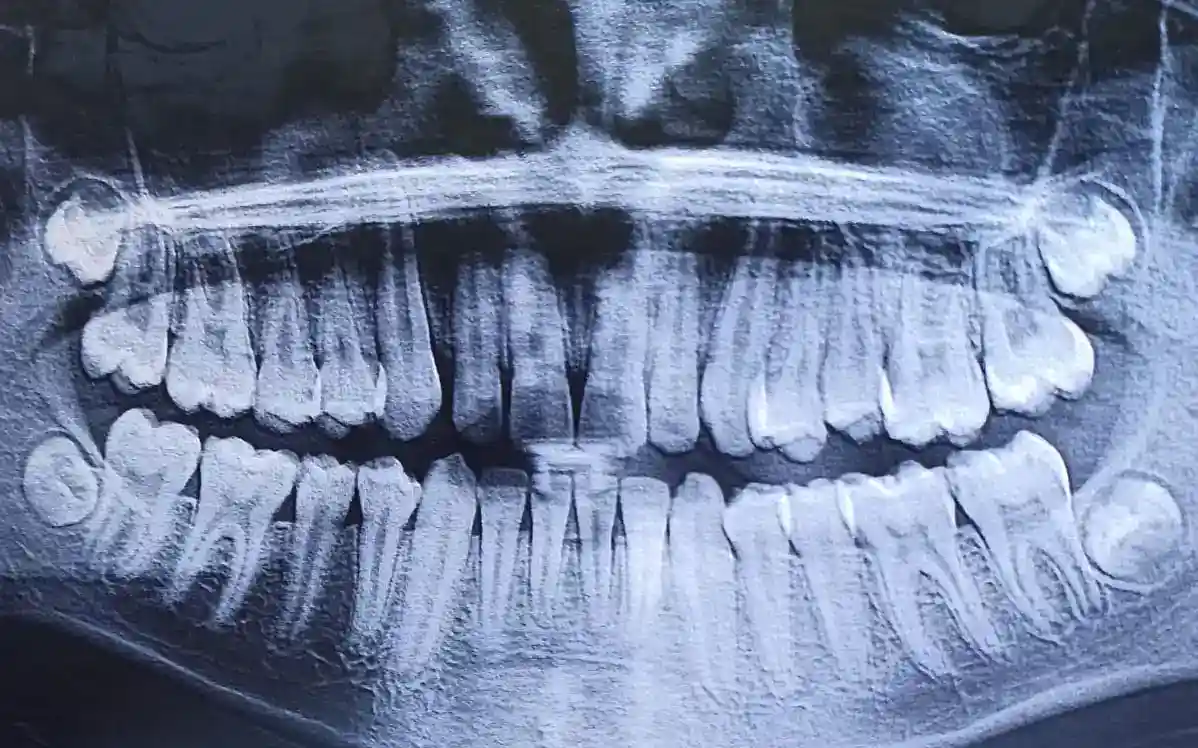

Evaluación Inicial y Diagnóstico

Antes de realizar una pulpotomía, es fundamental llevar a cabo una evaluación detallada del diente afectado. Esto incluye un examen clínico y radiográfico para determinar el alcance del daño y confirmar que la pulpotomía es el procedimiento más adecuado.